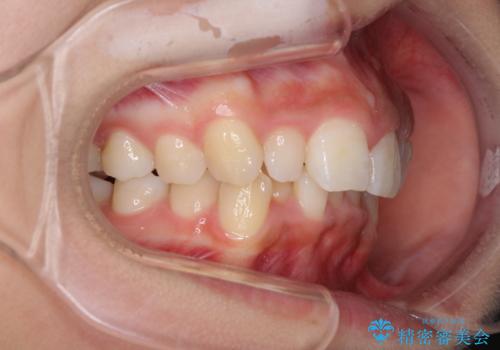

前歯のデコボコを治したい インビザラインによる矯正治療

- 前歯のデコボコ気になるとのことで来院された患者様です。

上下顎ともに歯列全体の後方移動とIPR(歯と歯の間を削る)によってデコボコが解消するように設計し、インビザラインにより治療を行うこととしました。

上顎左右前歯に矮小歯があるため、上顎の奥歯は下顎に対して相対的に前方に位置することになりました。

それでも奥歯の咬みにくさはなく、患者様には大変満足していただきました。